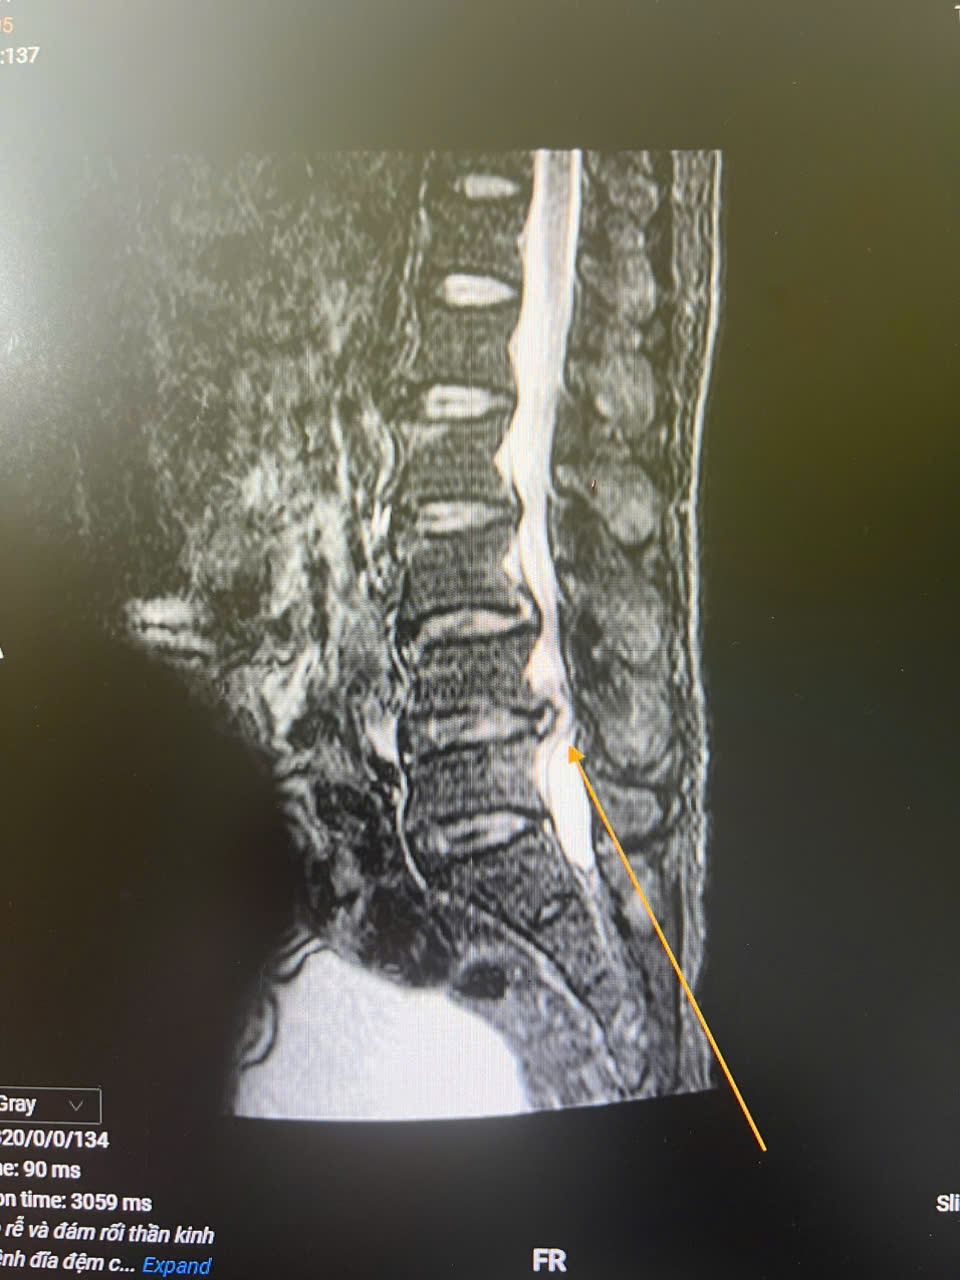

Ảnh 2: Cảnh báo biến chứng nguy hiểm từ thoát vị đĩa đệm, hẹp ống sống

Sau can thiệp, tình trạng bệnh nhân ổn định tốt, chức năng tiểu tiện cải thiện rõ rệt, cảm giác tê bì giảm đáng kể, vận động chân phải đang dần hồi phục.